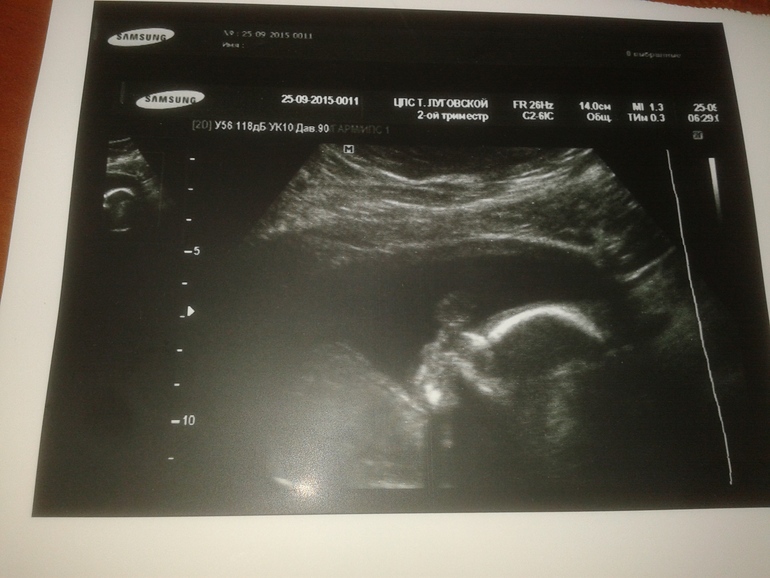

Была у меня запись на УЗИ на завтра, мне звонят из клиники. что не могут принять, я психанула и позвонила в другую клинику, записалась на 3.10.

В заключении слов много, но основное для истории и статистики:

БПР 47мм

ЛЗР 61мм

ОГ 172мм

Цефалический индекс 77

Диаметр груд клетки 43мм

ОЖ 142мм

Длина плеча 30мм

Длина бедра 31,6мм

Вес 309гр

Все органы на месте. все соответствуют сроку

ЧСС 138

Плацента по левой задней стенке, сосудов 3, толщина 25мм, зрелость 0-1ст, количество вод нормальное

Шейная складка 2,5мм

По данным УЗИ поставила ПДР 06/02/2015

Малышу нравится ручки держать у головы, все узи такая поза была